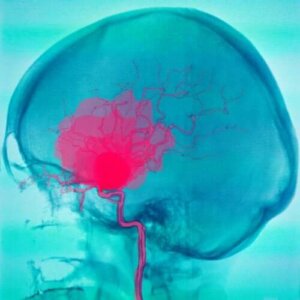

Hjernehinneblødning

Hjernehinneblødning er når blodet samles mellom spindelvevshinnen og pia mater. Blodet kommer vanligvis fra arterier og det kan ha mange forskjellige årsaker. Det vanligste er en sprukket aneurisme. Det kan imidlertid også ha andre årsaker.

Aneurismer kan komme med hodepine eller til og med epileptiske anfall før de sprekker. I opptil en tredjedel av tilfellene kan utløseren være noe fysisk med en emosjonell komponent. I tillegg kan det skje av å være i solen for lenge.

Blødningen begynner når de sprekker. Vanligvis skjer dette hos personer mellom 40 og 60 år og er knyttet til følgende symptomer: